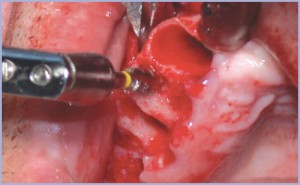

La prima fase chirurgica ha portato all’inserimento di 16 impianti (8 nell’arcata inferiore e 8 nell’arcata superiore), di cui 12 con diametro di 3,3 mm e 4 da 4,1 mm. Il posizionamento implantare nei settori laterali di destra del mascellare superiore e della mandibola ha richiesto, visto l’esiguità dei diametri ossei vestibolo-orali, un intervento di espansione di cresta(7) effettuato con strumenti rotanti (frese) e manuali (scalpelli, osteotomi: lanceolati e compattatori) (figg. 4-6).

- Figg. 4, 5, 6 – Intervento di espansione di cresta effettuato con strumenti rotanti e manuali

- Fig. 5

- Fig. 6